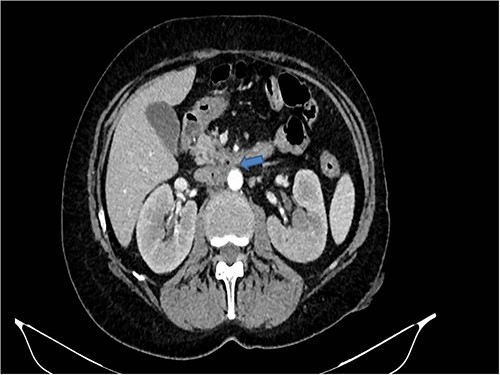

Therefore, given the persistence of the septic state and the radiological findings, the patient underwent laparotomy. Dense retroperitoneal fibrosis surrounded the IVC and the third section of the duodenum (Fig. 3). After complete mobilization of the duodenum with exposure and preparation of the entire subhepatic inferior caval vein and the two renal veins, the duodenal incision located at the level of the posterior wall of its third portion and the caval vein were sutured (Fig. 4). The cholecystectomy with Kehr drainage placement to protect the bowel suture and a jejunostomy were performed.

The complete kocherization of the duodenum (1) allowed to better identify the site of the fistula (2) and of the caval thrombus (3) allowing an adequate control of the left renal vein (4).